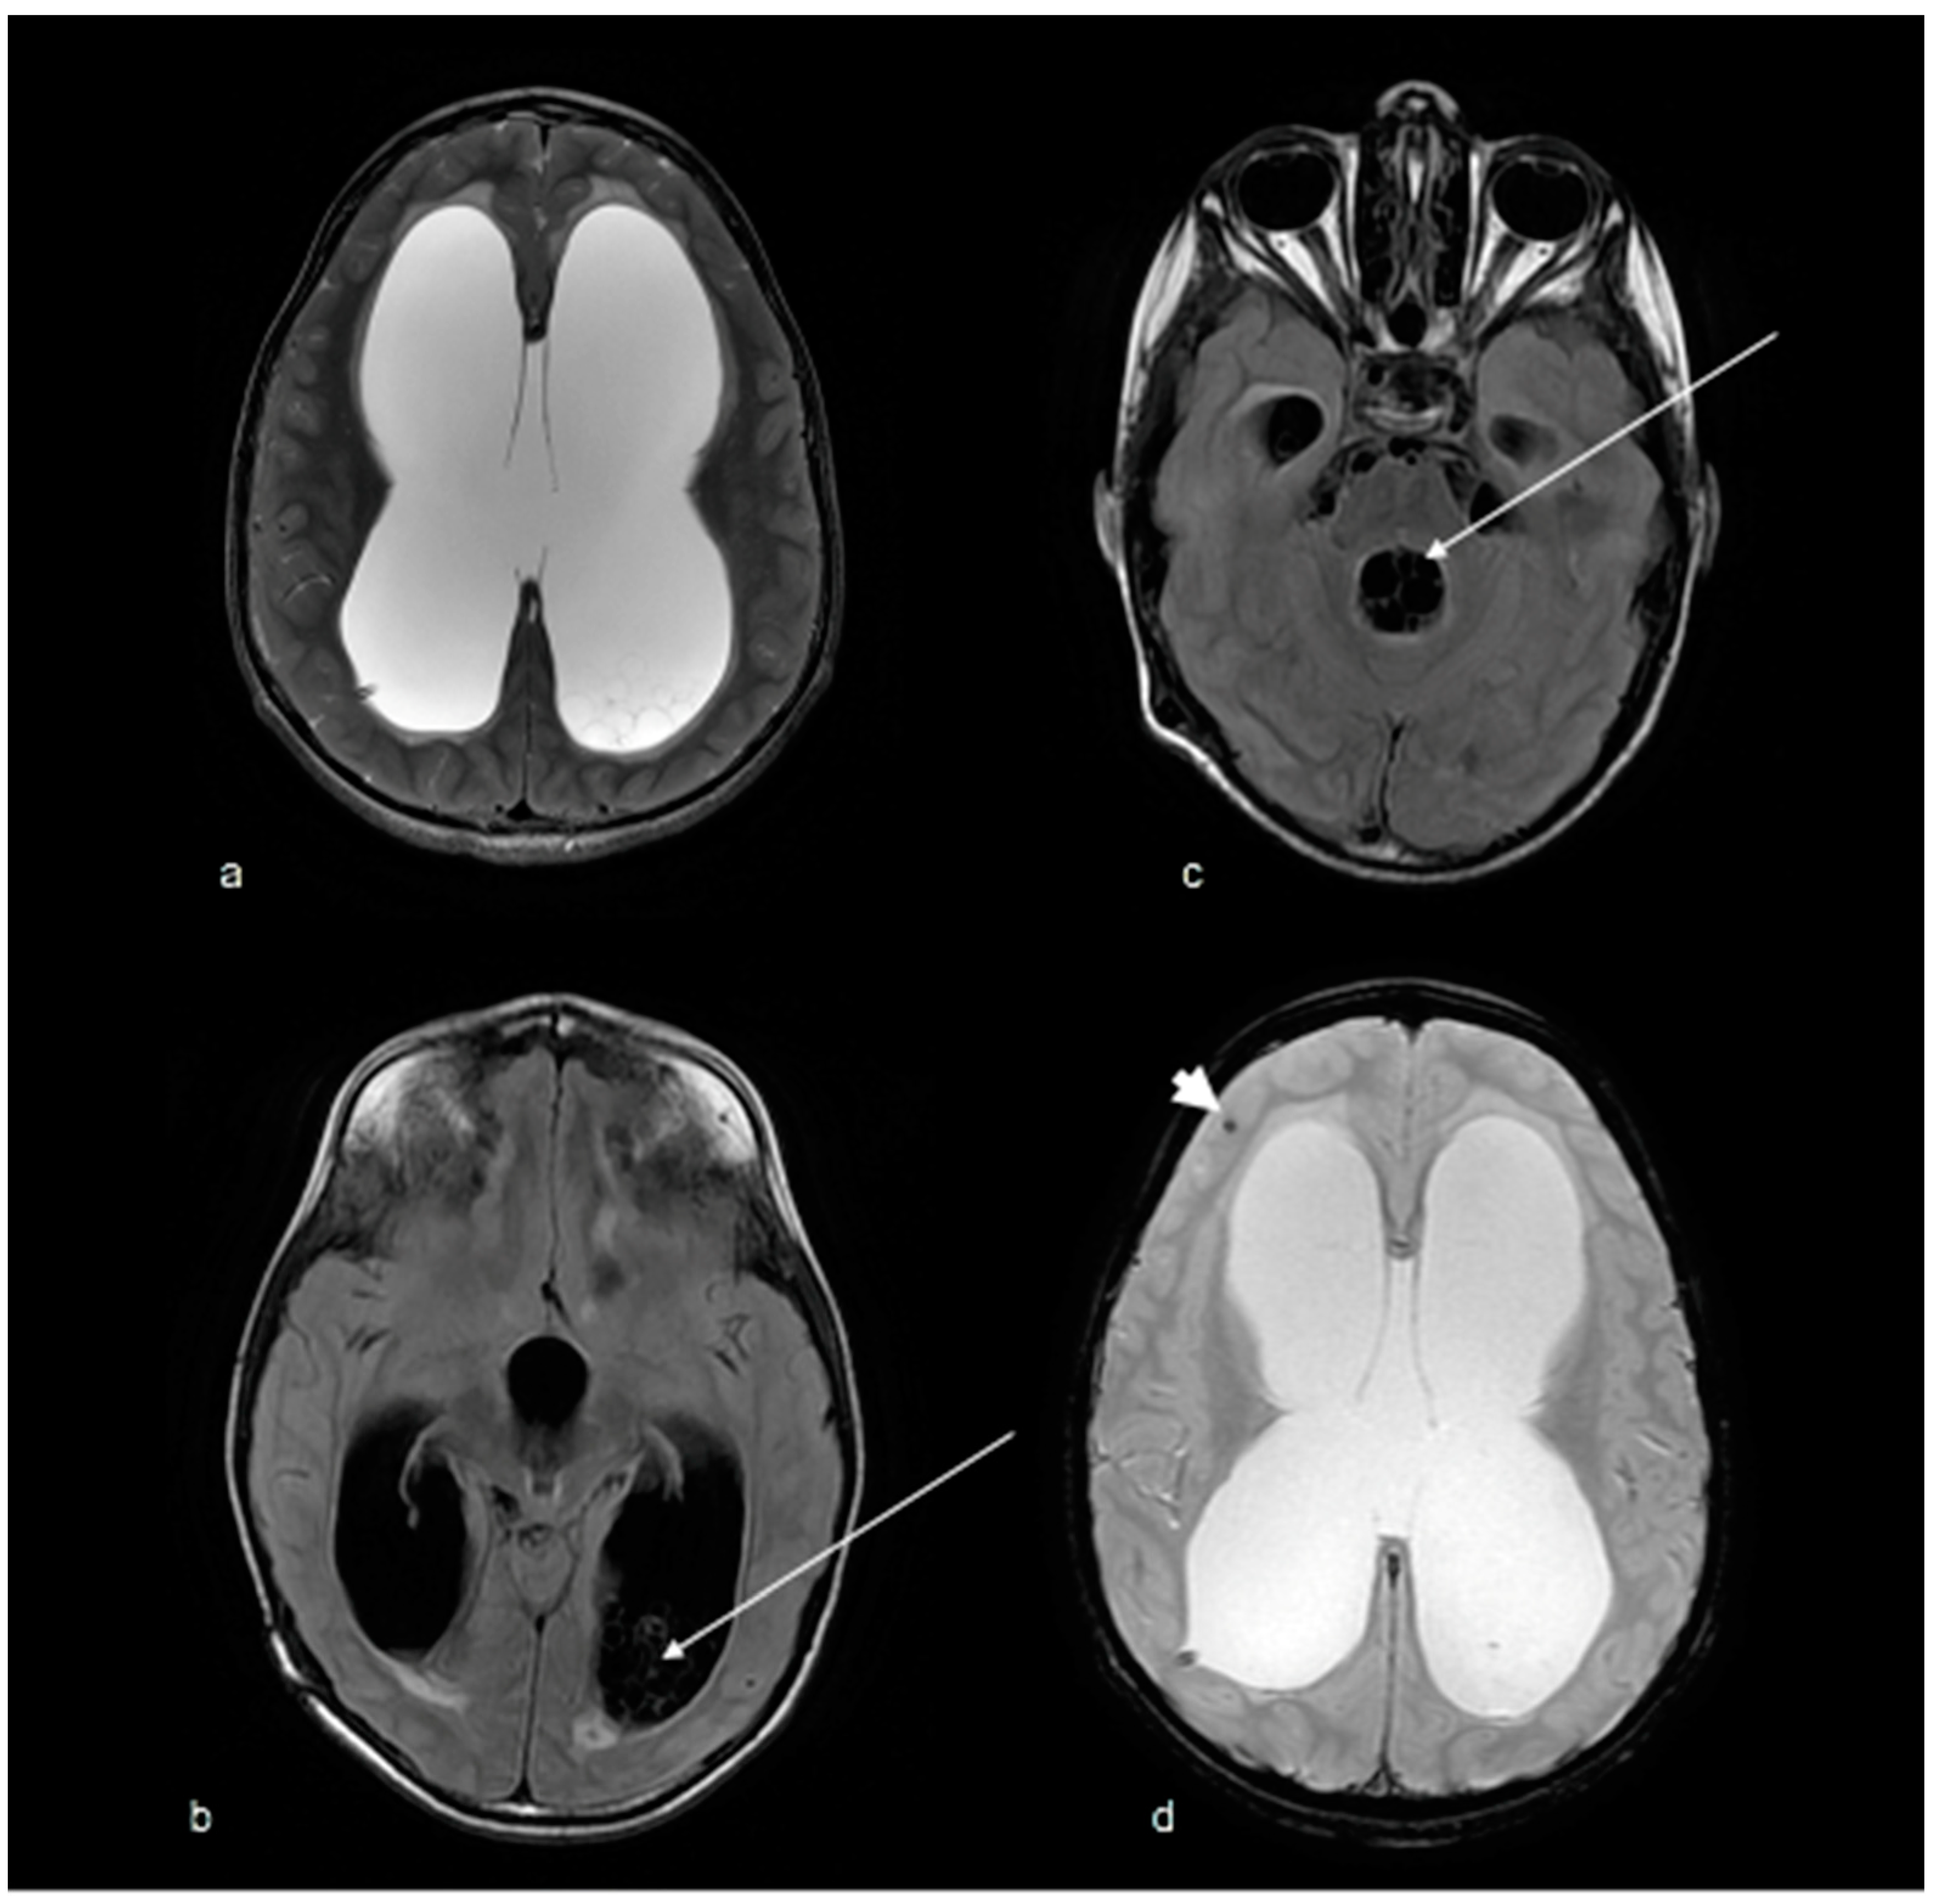

2. Case Report